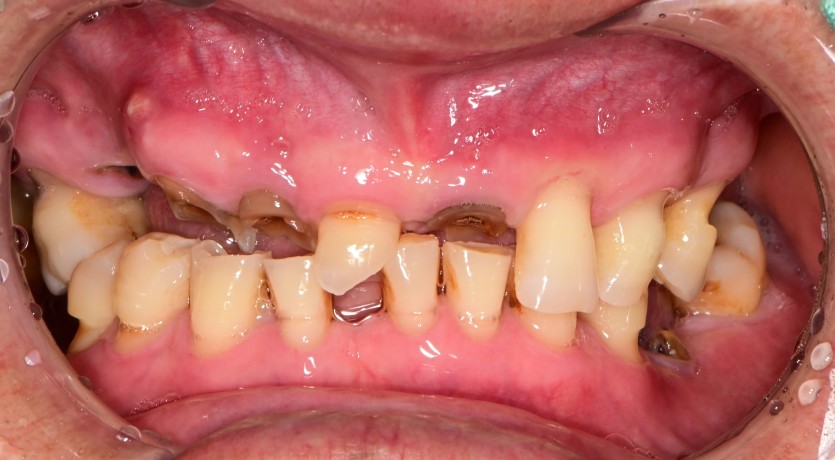

만 66세 전체 임플란트 증례(하악 일부)

전체 임플란트 증례입니다. (하악 일부)

16개의 임플란트로 완성하였습니다.